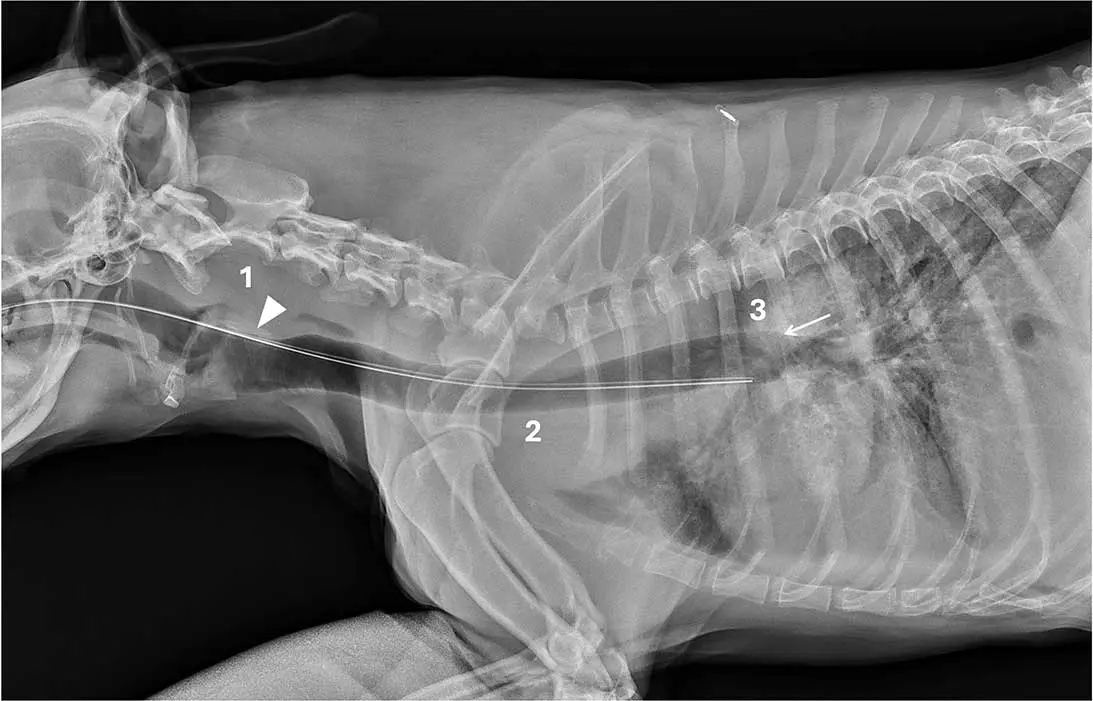

Figure 1. Case one.

To identify the landmarks in the radiographs in Figures 1-5, arrowheads indicate the lamina of cricoid cartilage of the larynx (when included), and arrows show the dorsal wall of the carina. Additionally, numbers highlight the three criteria and landmarks: (one) larynx, (two) tracheal lumen, and (three) carina.

Case one

This lateral cervical and thoracic radiograph (Figure 1) of a dog includes the larynx and shows:

- Dorsal passage of the tube at the level of the lamina of cricoid cartilage (arrowhead).

- Incomplete tracheal overlap.

- A position dorsal to the carina (arrow).

Laryngeal cartilages tend to mineralise in older dogs and occasionally in younger large-breed dogs, as in this case, with the lamina of cricoid cartilage typically the most apparent.

Interpretation. Correct oesophageal placement. All criteria were met, so the tube was safely positioned for feeding.